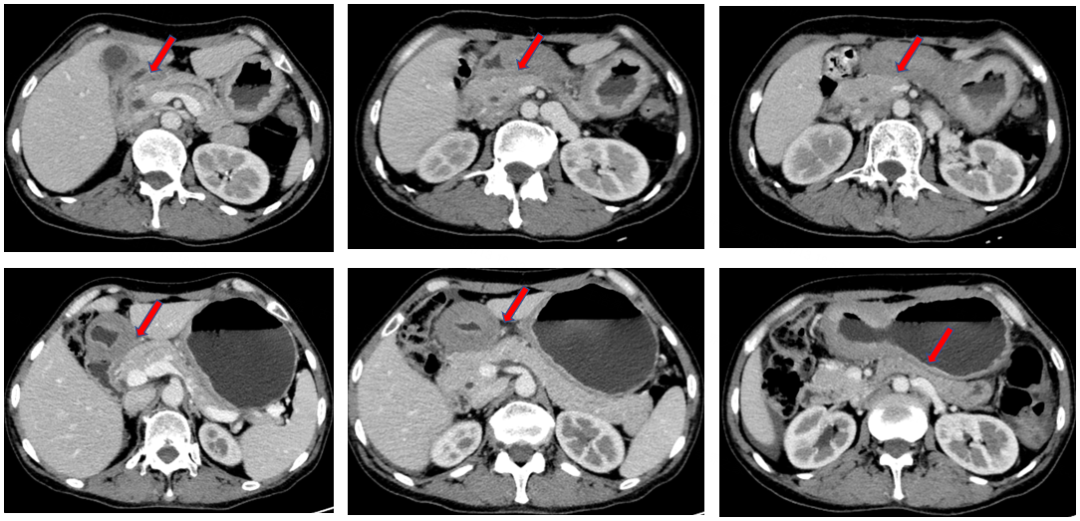

胃癌晚期肝转移化疗前后ct--典型病例梁xx,_治疗

图片尺寸1280x960